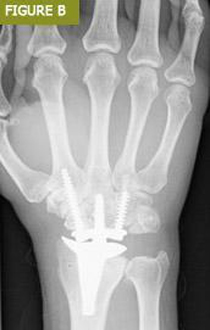

Daha önce de belirtildiği gibi, hasarlı veya tahrip olmuş eklemlerde eklem artroplastisi endikedir. Bu dejenerasyona bağlı olabileceği gibi daha önceki bir yaralanmanın sonucu da olabilir (Şekil A ve B). Romatoid artrit ve gut gibi inflamatuar artritlerin artan prevalansı ve birçok kişi tarafından benimsenen varlıklı yaşam tarzları ile eklem kıkırdağı dejenerasyonunun bir sonucu olarak ağrılı, şişmiş eklemler yaygın bir olaydır. Bu durumlarda eklem artroplastisi ağrıyı azalttığı ve hareket aralığını iyileştirdiği veya en azından koruduğu için faydalı olacaktır.